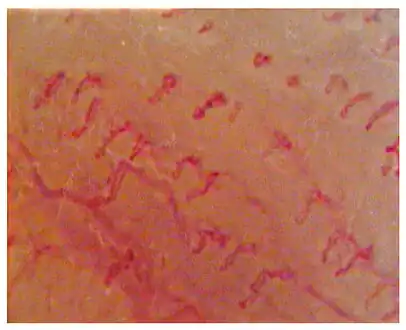

Capillaroscopic evaluation in Burning mouth syndrome -

Geographic tongue (benign migratory glossitis)

- Geographic tongue (benign migratory glossitis) - a common disorder which occasionally causes a burning sensation but is usually painless. Irregular patches of depapillation form on the tongue giving the appearance of a map. The cause is unknown.

- Burning mouth syndrome - this chronic pain disorder commonly involves the tongue. In reflection of this, some of the synonyms for the condition include tongue-specific terms such as "glossodynia" or "burning tongue syndrome". Burning mouth syndrome is characterized by chronic burning sensation on the tongue and other oral mucous membranes in the absences of any identifiable signs or causes.